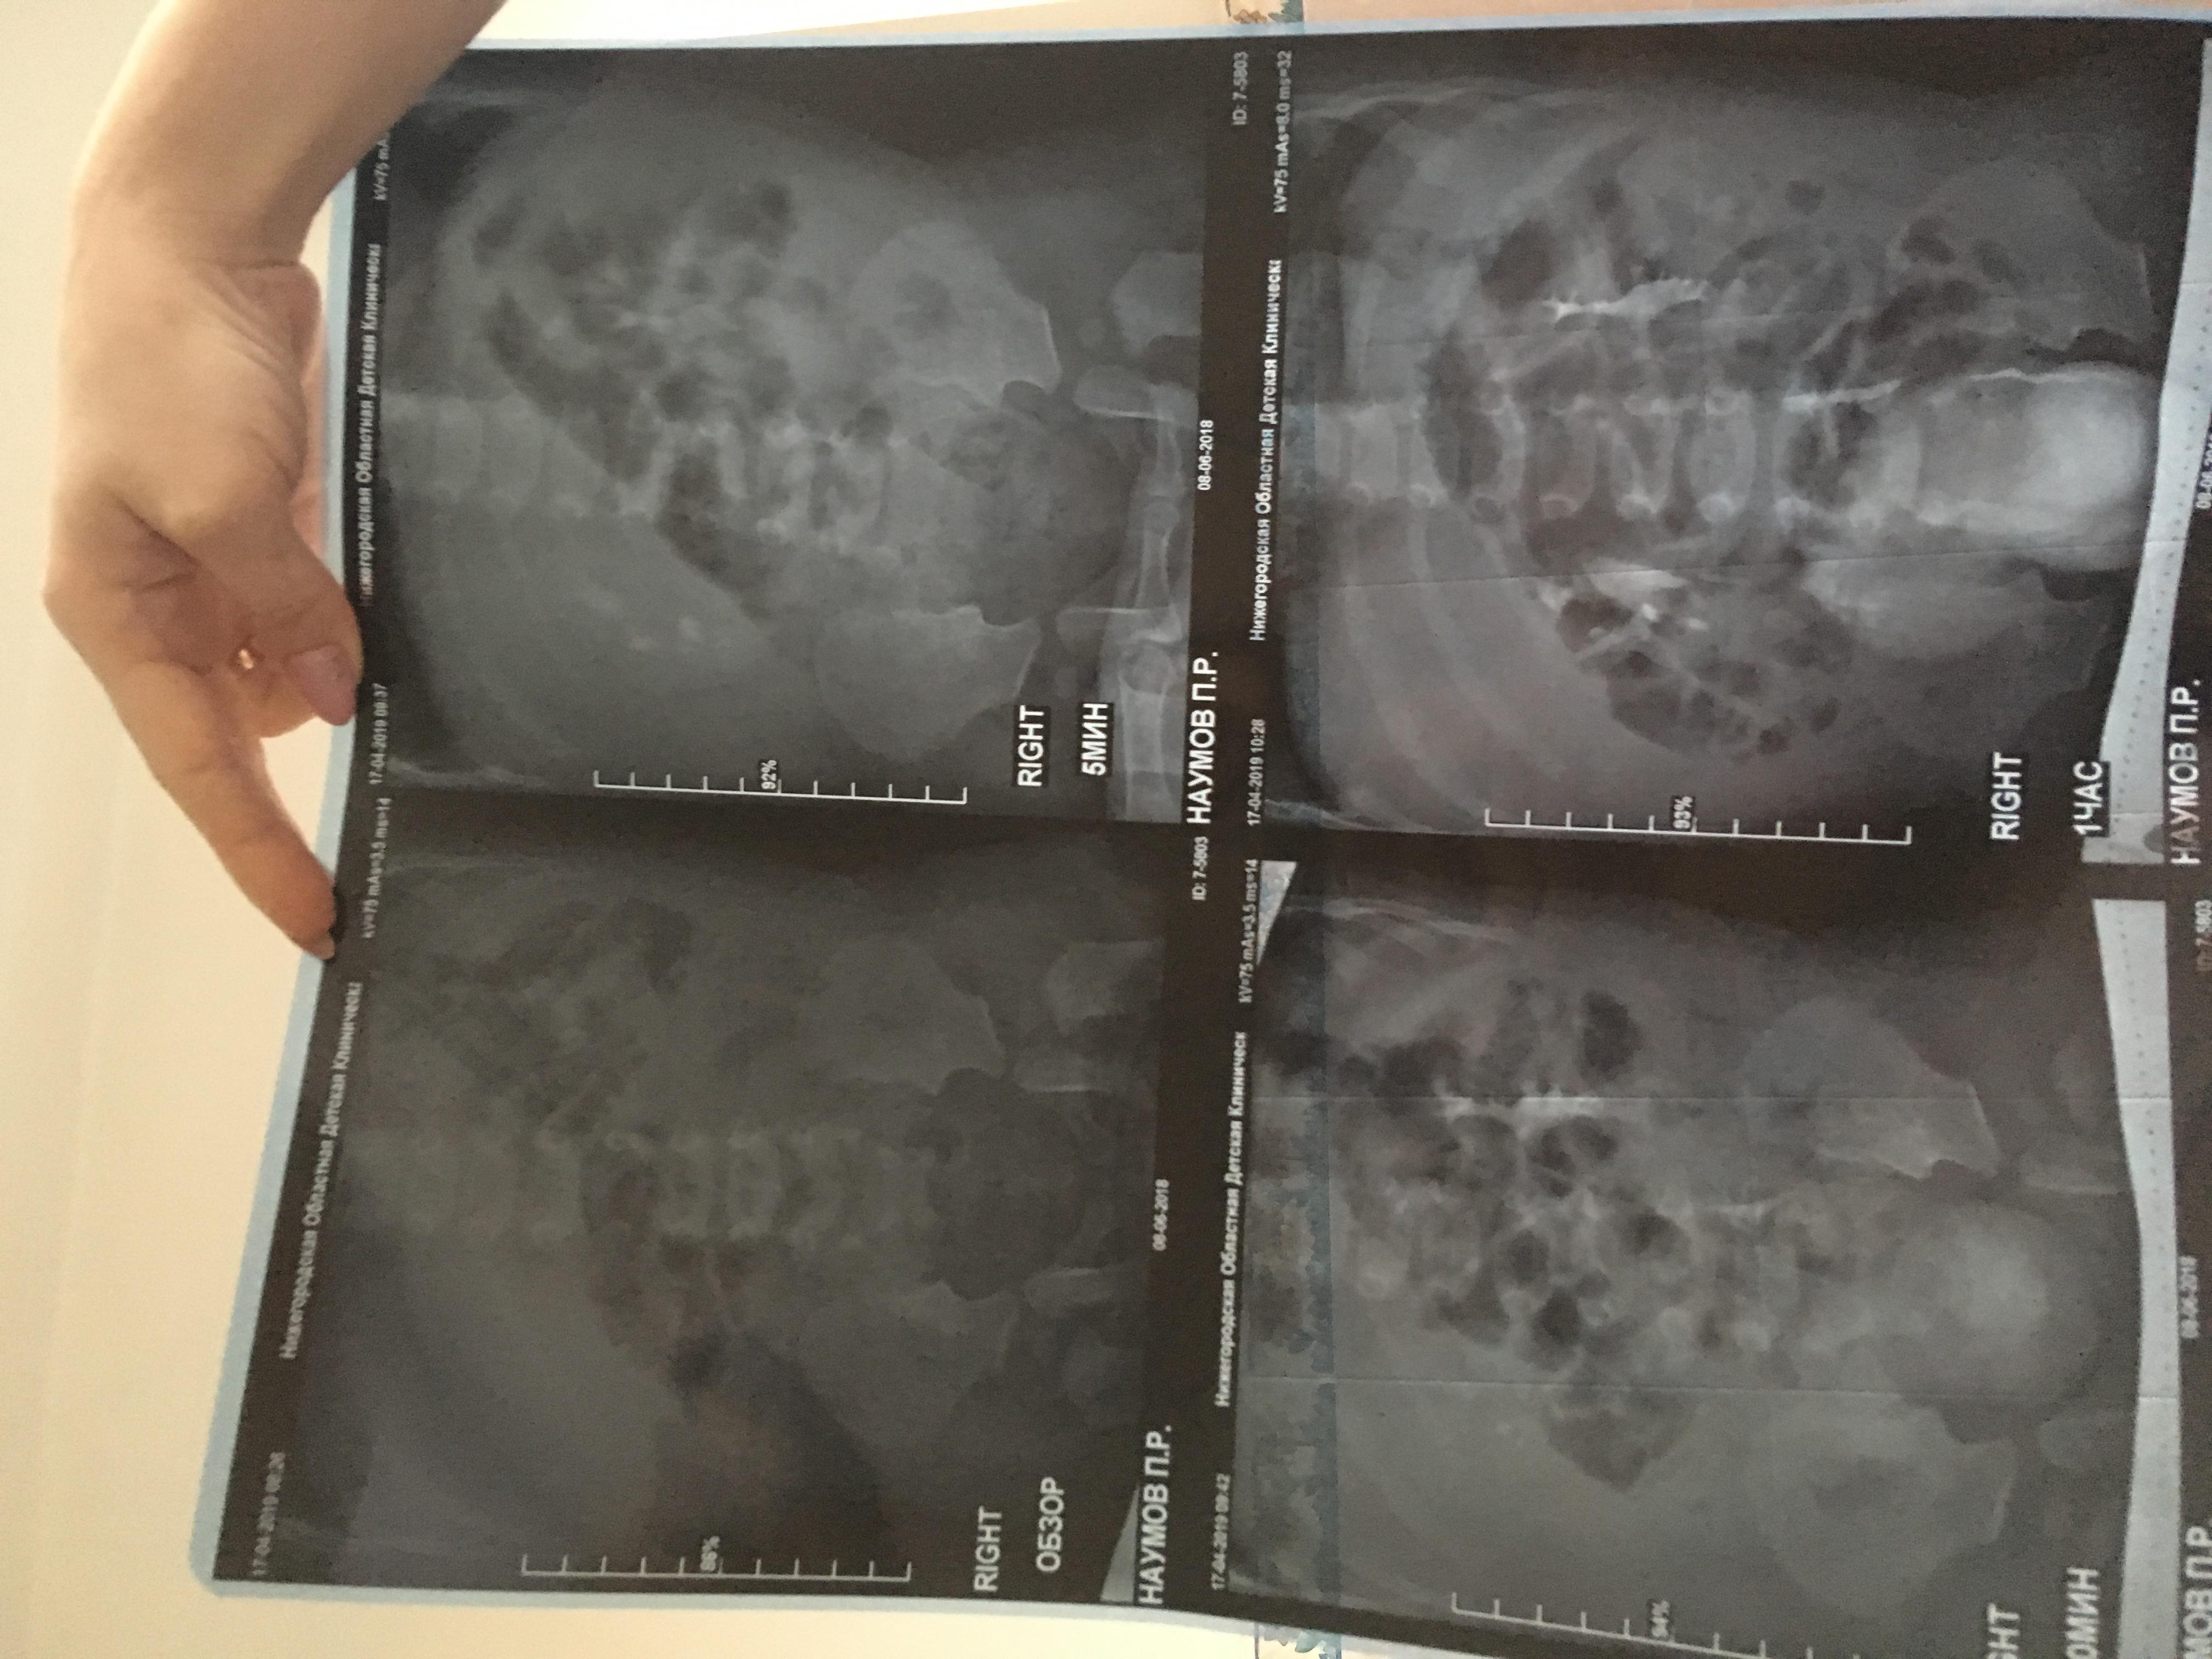

Здравствуйте , с Рождения поставлен диагноз уретерогидронефроз , пмр4 ст. Пол года назад сделали операцию по Коэну, но улучшений нет , рефлюкс стал 3 ст, а функция почки снижена . Лечащий хирург сказал, что ничего предпринимать не нужно, только наблюдение и высокая вероятность сморщивание почки и в последствии ее удаление. Скажите пожалуйста действительно ли уже не спасти почку ?!

Прилагаю снимки до операции и после операции.